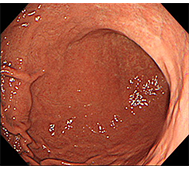

食道がん

進行がんの場合は、嚥下困難などを認めます。

- 手術的治療 :内視鏡治療ができない病期の食道がんに対しては、根治術として食道切除術+リンパ節郭清が行われてきました。

- 化学放射線療:近年、食道がんに対する化学療法と放射線療法の併用療法は、手術加療以外の根治的治療とし広く行われてきています。